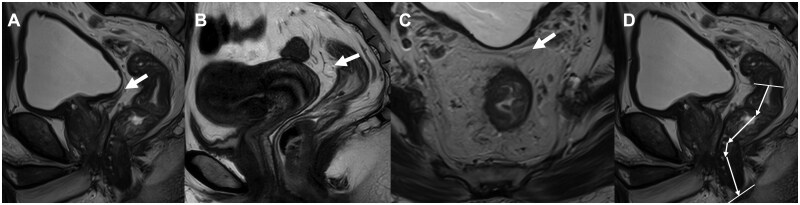

Background: Tumor location affects rectal cancer management, but no consensus exists on criteria. The anterior peritoneal reflection (aPR), an anatomical landmark, shows potential for defining tumor location but requires clinical validation. This study evaluated the utility of aPR in guiding neoadjuvant chemoradiotherapy (nCRT) decisions and predicting lateral lymph node (LLN)/distant metastasis patterns.

Methods: This single-center retrospective cohort analyzed data from Peking Union Medical College Hospital (Beijing, China) between January 2016 and August 2022. Magnetic resonance imaging (MRI)-measured aPR parameters were pathologically validated. Patients were stratified by aPR-based definition and tumor height (10 cm). Kaplan-Meier survival curves, log-rank tests, and Cox regression were used for prognostic analysis.

Results: Among 588 patients (439 tumors ≥5 cm from the anal verge), MRI identified aPR with an accuracy of 95.4%. For tumors ≥5 cm, aPR-defined middle-to-low rectal cancer showed lower 3-year disease-free survival (DFS) rate than the upper rectal cancer (P = 0.010), while their 3-year overall survival (OS) rates were comparable. Conversely, 10-cm-defined classification showed no DFS or OS differences (both P > 0.2). Cox regression confirmed aPR-defined classification as an independent DFS predictor (HR = 3.19, P = 0.014), while 10-cm classification was non-predictive. nCRT with tumor regression grade (TRG) 0-1 trended toward improved DFS compared with direct surgery (HR = 0.56, P = 0.072). The independent protective effect of nCRT with TRG 0-1 for DFS was exclusive to the aPR-defined middle-to-low rectal cancer subgroup (HR = 0.45, P = 0.026) and not observed in the 10-cm subgroup. aPR-defined classification was independently associated with LLNs on MRI and postoperative pulmonary metastasis.

Conclusion: aPR may guide nCRT decision-making and predict LLN metastasis and postoperative distant organ metastasis.